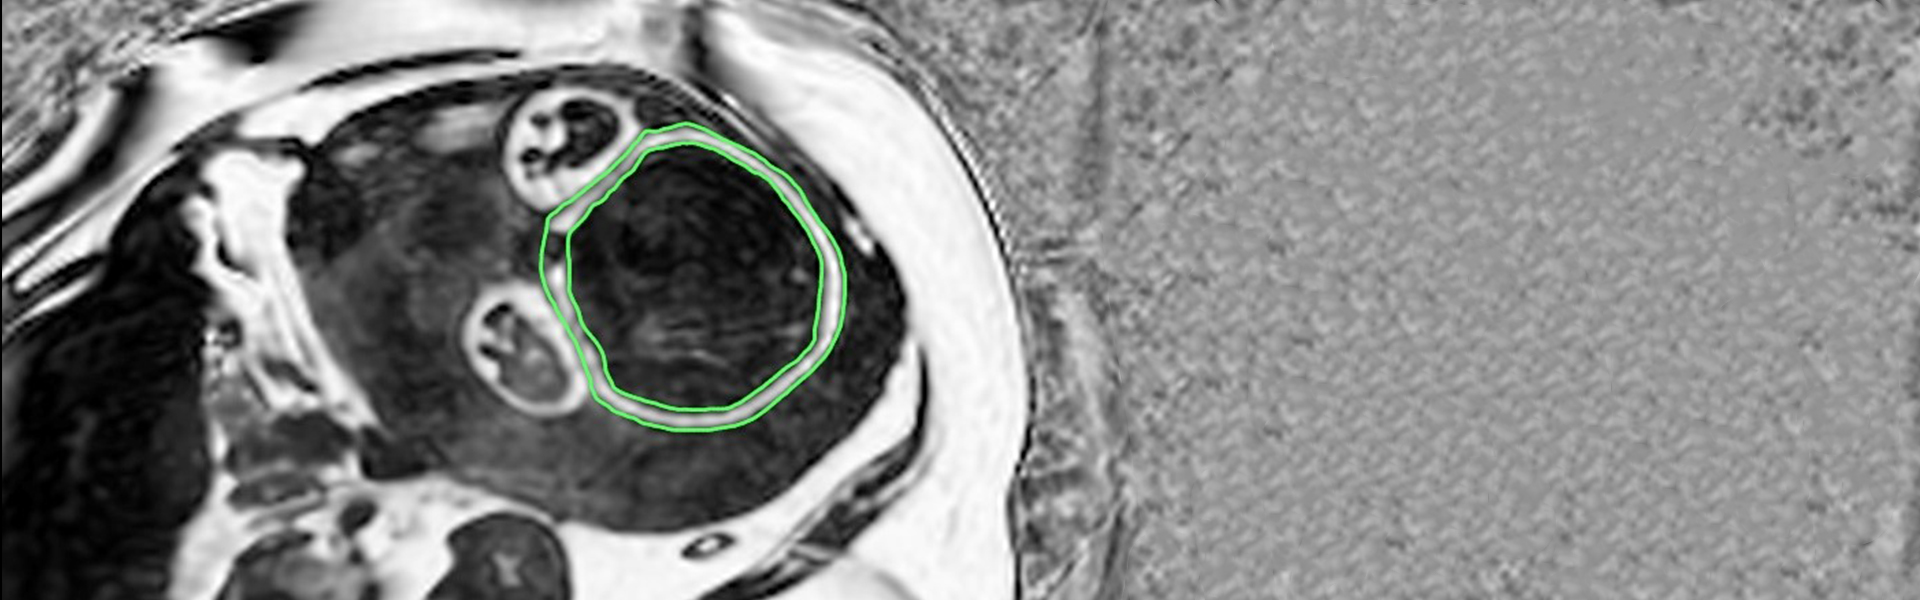

The focus of our research is Parallel Magnetic Resonance Imaging (PMRI): involving the development of coil arrays, pulse sequences and image reconstructions; Spectroscopic imaging with IDEAL; Abdominal imaging, particularly of the liver and fetus, with combined PMRI and IDEAL